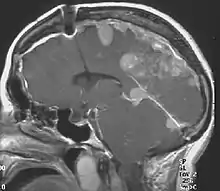

The so-called acoustic neuroma of NF2 is in fact a schwannoma of the nervus vestibularis, or vestibular schwannoma. The misnomer of acoustic neuroma is still often used. The vestibular schwannomas grow slowly at the inner entrance of the internal auditory meatus (meatus acousticus internus). They derive from the nerve sheaths of the upper part of the nervus vestibularis in the region between the central and peripheral myelin (Obersteiner-Redlich-Zone) within the area of the porus acousticus, 1 cm from the brainstem.

Bilateral vestibular schwannomas are diagnostic of NF2.[15]